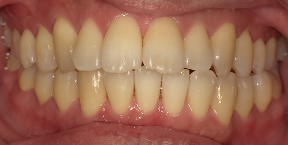

29歳女性のビフォーアフター

| 診断 | 叢生(デコボコがある状態)、過蓋咬合 |

| 治療方針 | インビザラインシステムにて主にIPR(歯と歯の間をわずかに削合してスペースを獲得する方法)を組み込んだ動的矯正治療を行い、叢生を改善後、保定を行う。臼歯部の咬合関係はプランの関係上維持して叢生と前歯部の咬合改善を目指した。 |

| 治療費 ※ | 60万4千円(診断、型取り、PMTC、保定装置を含む料金) |

| 治療期間 | 1年5か月 |

| リスク | 1日20時間以上マウスピースを使用できない場合、歯が動かない可能性がある。装着時や食事時に痛みを伴う。歯肉退縮や虫歯になるおそれがある。また、指導通りに装着できていない場合や適切なブラッシングが出来ていないとそのリスクが高くなる。歯根が短くなることがある。ごくまれに歯の神経が損傷してしまうことがある。過去にぶつけたり深い虫歯治療をしたことがあるとそのリスクはやや高くなる。矯正後には保定装置が必要。適切な使用ができない場合、後戻りの原因となる。将来的に歯並びが動いて再矯正が必要な場合がある。親知らずが正常に生えていない場合、その可能性がやや高くなる。 |

※ 治療費は、治療当時の費用で、現在の費用と異なる可能性があります。現在の費用は治療費のページでご確認くださいませ。